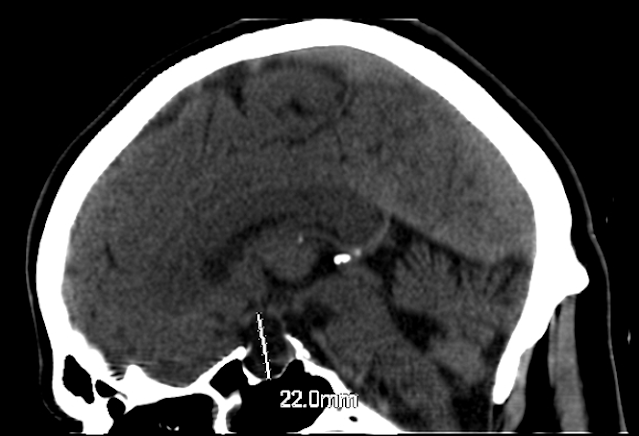

Precisamente la curiosidad por la que decidí hablar hoy de esta fractura, además de porque en una de las últimas guardias vi una, es porque radiologicamente la imagen que se aprecia tiene un nombrecillo curioso, cosa que ahora se gracias al traumatólogo que estaba de guardia y me dijo como llamaban ellos pijoteramente a la imagen de fractura que veía: "PooPing Duck", o traducido al cristiano "pato cagando" XD

En este signo, el fragmento dorsal de fractura representa la «caca» del pato. El pato es creado por la confluencia de las imágenes de los huesos de la fila proximal del carpo, que incluyen: el escafoides (cabeza y cuello del pato), semilunar (cuerpo y alas del pato) y la cortical dorsal del triquetrum (cola del Pato).